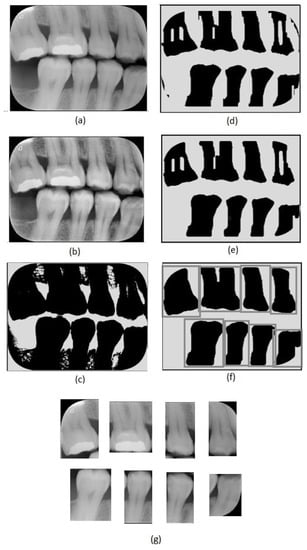

Figure 2.

Image preprocessing steps: (a) original image, (b) adaptive histogram equalization, (c) Otsu’s thresholding, (d) erosion, (e) closing, (f) dilation and tooth region definition, (g) tooth images obtained.

The first step of the proposed method consists of an adaptive equalization operation (Figure 2b), performed to enhance the image’s details, allowing an easier differentiation between background and tooth areas. For this operation, we used the adaptive histogram equalization [21]. This operation considers parts of the image rather than the entire image. It uses the histograms of these parts to calculate local equalizations. Note that in the adaptive equalization, the histograms are created based on a defined neighborhood window. In this work, we tested variations of window sizes and achieved the best visual result using an 8 × 8 window.

In the achieved equalized image, the tonalities of teeth and background areas differ substantially. In this way, binary images can be obtained from the equalized images using a thresholding process. In this work, we used the Otsu thresholding technique [22].

Although the thresholding process properly separates most of the tooth areas from the background areas, some small regions are incorrectly assigned in both areas. This can be easily corrected using morphological operators [23]. Note that, in the binary image resultant from the thresholding (Figure 2c), the tooth areas are of large regions with few flaws. On the other hand, the incorrectly included regions are small and irregular, which can be eliminated easily using morphological operations. Considering the thresholded image (Figure 2c), we first applied an erosion using a structuring element that presents a rectangular shape and size of 130 × 20 (Figure 2d). We chose this specific element for erosion after evaluating the shapes of the incorrectly included regions. On the one hand, smaller elements do not eliminate the undesirable regions entirely; on the other hand, larger elements accidentally remove parts of the identified teeth regions. In our investigation, we also observed that using uniform, symmetrical structural elements, e.g., squares or circles, led to the union of regions of contiguous teeth that were close together. In the opening operation, a circle with a radius of 20 pixels was used as the structural element (Figure 2e). This operation eliminated the remaining undesirable parts. Finally, we applied dilation with a circle with a radius of 15 pixels as a structuring element. This dilation recovered the borders in the tooth areas that were accidentally removed in the erosion operation.

After removing the incorrectly included regions, the binary images are only composed of teeth areas (large and black) in a white background. In the resultant binary image, each area refers to a different tooth. These areas are considered the regions of interest. We created new images covering each tooth defined by the bounding boxes around the regions of interest (Figure 2f). Thus, we repeatedly cropped the original bitewing image, using the limits defined by the bounding boxes to obtain individual images for each tooth (Figure 2g). Data processing was performed using Python and the scikit-image library.